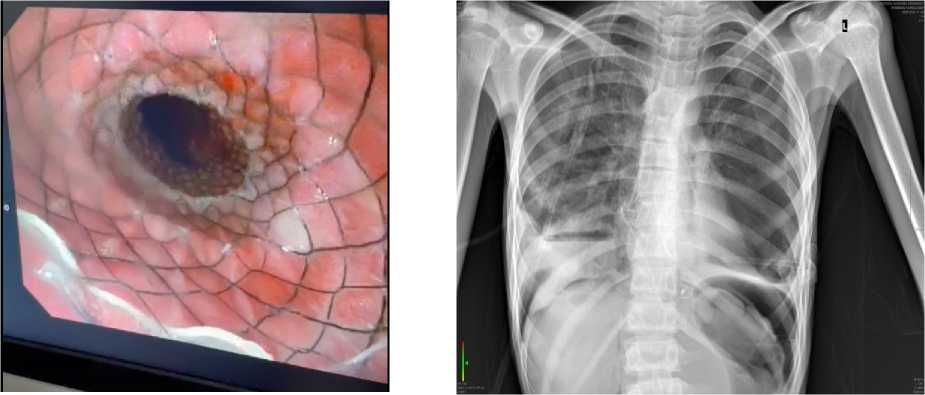

III этап — стентирование пищевода. В связи с сохраняющейся тяжёлой дисфагией и недостаточной эффективностью предыдущих этапов лечения принято решение о выполнении эндоскопического стентирования пищевода (рис. 1). Установка пищеводного стента была направлена на поддержание адекватного просвета дистального отдела пищевода, стабилизацию достигнутого эффекта и обеспечение более устойчивого восстановления пассажа пищи.

В раннем послеоперационном периоде течение заболевания осложнилось развитием перфорации пищевода. Возникновение данного осложнения было обусловлено сочетанием тяжёлого исходного состояния пациента, выраженной дилатации и истончения стенки пищевода, а также наличием рубцовых изменений дистального отдела на фоне длительного течения ахалазии. Перфорация пищевода привела к распространению инфекционновоспалительного процесса за пределы органа и развитию тяжёлых системных осложнений. На фоне перфорации пищевода у пациента сформировалась эмпиема плевры, сопровождавшаяся нарастанием дыхательной недостаточности и признаками интоксикации (Рисунок 2). Инфекционный процесс быстро приобрёл генерализованный характер, что привело к развитию тяжёлого септического шока, сопровождавшегося выраженными гемодинамическими нарушениями и прогрессирующей полиорганной недостаточностью.

Рисунок 1. Эндоскопическое изображение пищевода: визуализируется установленный пищеводный стент

Рисунок 2. Обзорная рентгенография органов грудной клетки. В проекции средостения определяется рентгеноконтрастный пищеводный стент. В нижних отделах правого лёгочного поля визуализируется интенсивное затемнение с горизонтальным уровнем жидкости